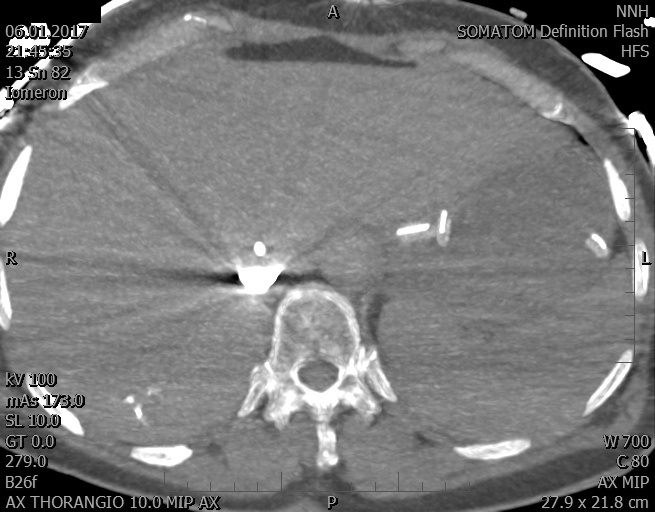

Video 2 - Echokardiograficky byla zjištěna těžká dysfunkce dilatační levé komory s nezvětšenou pravou komorou.Pro nejasnou příčinu zástavy jsme provedli i vyšetření výpočetní tomografií (CT), které vyloučilo plicní embolizaci (série 1 - soubory na konci článku). V den přijetí při přetrvávající oběhové nestabilitě byla nemocná opakovaně defibrilována pro fibrilaci komor se stabilizací rytmu po podání amiodaronu a mesocainu. Dle hemodynamických měření se jednalo o těžký kombinovaný šok. Vstupní laboratorní vyšetření bylo bez větších pozoruhodností. Posléze jsme doplnili anamnézu od příbuzných a zjistili, že pacientka užila do dvou hodin před srdeční zástavou první tabletu amoxicilinu na lehký respirační infekt. Při nevýtěžnosti vstupních vyšetření a nových anamnestických informacích jsme doplnili 14 hodin po kolapsu vyšetření koncentrace tryptázy v séru, která byla extrémně zvýšena (tabulka 2), což nás vedlo k podezření na anafylaxi.